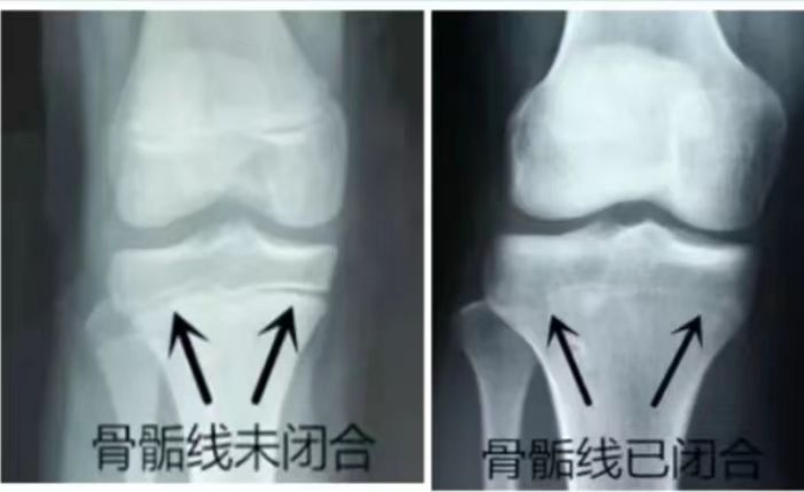

最简单的方法就是去医院的骨科拍张膝关节的X光片,就可以知道自己还能不能长高了。

如果骺板还清晰可见,就有继续长高的可能。但如果骺板已经和胫骨近端长在一起了,基本不可能继续长高了。